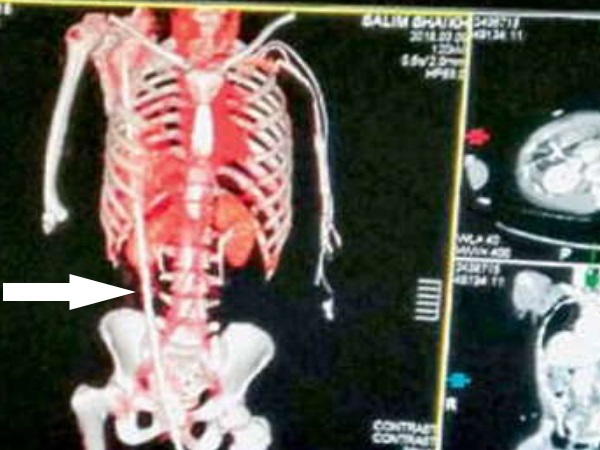

मुंबई। नासिक में भवन निर्माण के दौरान 9 फीट नीचे स्लैब में गिरे मजदूर सलीम शेख की जांघ के पास से घुसा सरिया उसके दाएं कंधे से बाहर निकल गया था। उसे गंभीर हालत में 200 किमी दूर मुंबई के जेजे अस्पताल में भर्ती कराया गया था। जहां पर घंटों की मेहनत के बाद 4 फीट का सरिया निकाला दिया गया। सरिया निकालने के लिए जेजे अस्पताल के 10 डॉक्टरों की एक टीम बनाई थी। फिलहाल सलीम अब स्वस्थ है।

अस्पताल प्रशासन ने बताया कि, 8 मार्च को सलीम शेख (33) लासलगांव में कन्स्ट्रक्शन का काम कर था। इस दौरान वह 9 फीट नीचे स्लैब पर गिर गया। स्लैब का सरिया उसकी जांघ में घुसकर लिवर, इन्टेन्स्टाइन और फेफड़े को पार करते हुए दाएं कंधे से बाहर निकल गया। यहां काम कर रहे मजदूरों ने सरिये को स्लैब से काटकर उसे पास के अस्पताल में भर्ती किया।

नासिक के जिला अस्पताल में भर्ती करवाया। जहां पर अत्यधिक खून बहने से उसके अंग कमजोर पड़ते जा रहे थे। सरकारी अस्पताल के डॉक्टरों ने उसे किसी बड़े अस्पताल में भर्ती करने के लिए कहा। इसके बाद सलीम को 9 मार्च को जेजे अस्पताल में भर्ती करवाया गया। जहां पर सर्जन डॉ अमोल वाघ की निगरानी में उसे रखा गया। डॉक्टरों ने सलीम के पेट और सीने में एक-एक लेप्रोस्कोप डालकर देखा कि जख्म कहां है और लिवर, फेफड़े से सरिया निकालने के लिए कंधे से उसे खींच लिया और फिर आंतरिक सर्जरी की गई, जो करीब पांच घंटे तक चली।

डॉ अमोल वाघ ने बताया कि सलीम के शरीर में सरिया उनके प्राइवेट पार्ट के पास से घुसकर कंधे के ऊपर से निकल गई थी। 4 फुट की सरिया सलीम की आंतें , लिवर, फेफड़े और पेट के बीच की लेयर को छेदते हुई निकल गई थी। ऐसे में सरिया निकालना काफी मुश्किल था। मरीज की सभी जांच के बाद हमने धीरे-धीरे सरिया बाहर निकाली।